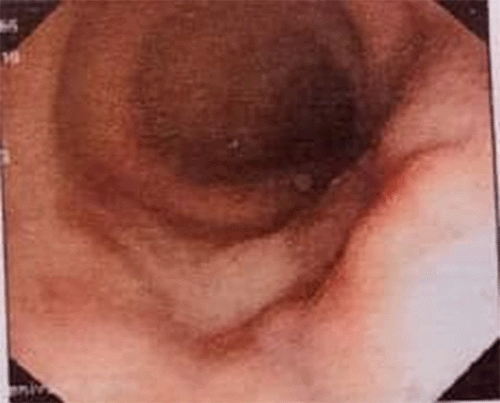

Figure 2. Colonoscopy Showing Nodular Area in Descending Colon. Published with Permission

A 42-year-old man presented with complaints of left-sided abdominal pain associated with bleeding per rectum of 30 days duration. He underwent a laparotomy for resection of a retroperitoneal malignant tumor in 2009; on histopathological examination, the tumor was consistent with malignant fibrous histiocytoma. The physical and rectal examination did not reveal any abnormalities. Complete blood count, serum electrolytes, creatinine, and urea were within the normal range, and screening for viral markers was negative. He underwent abdominal ultrasonography, which revealed a large rounded lesion, predominantly hypoechoic lesion of size more than 7.2 × 7.7 cm in the left hemipelvis, anterior to left iliac vessels and close to the midline. The lesion showed increased vascularity, and the site of the origin of the lesion could not be defined. Colonoscopy showed a nodular area with evidence of luminal compression and a visible vessel with an intermittent spur. Therapeutic intervention was not performed as there was no active bleeding.